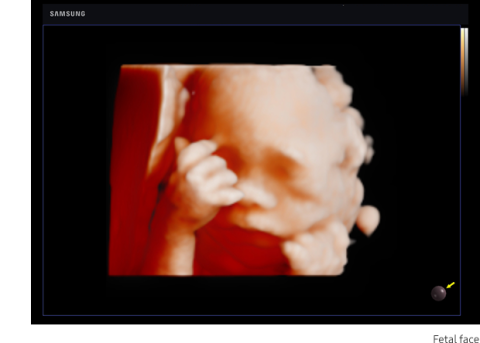

RealisticVue™ displays high resolution 3D anatomy with exceptional detail and realistic depth perception. User selectable light source direction creates intricately graduated shadows for better defined anatomical structures.